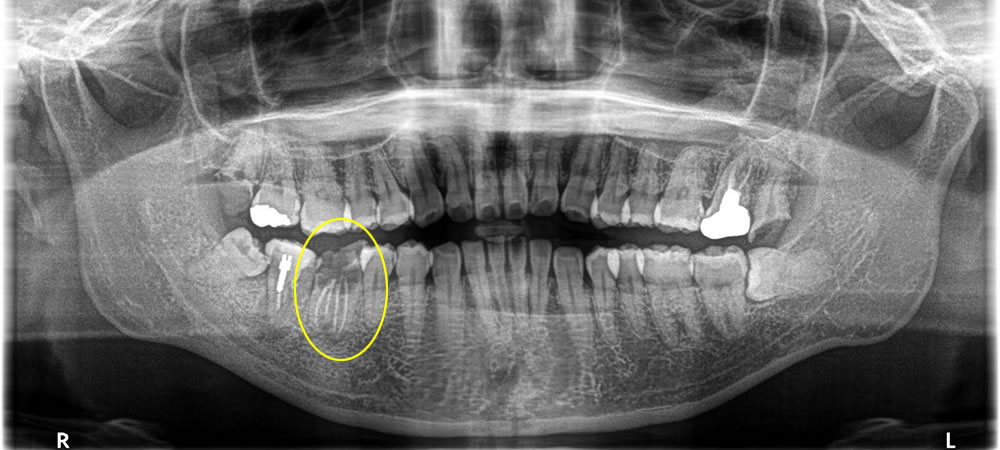

保存不可能な歯を抜歯後にインプラント治療を実施した症例

年齢

30代

性別

女性

症例を見る